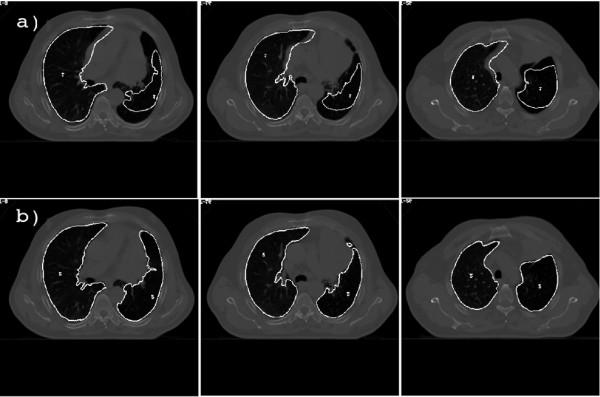

The study of lung parenchyma anatomical modification is useful to estimate dose discrepancies during the radiation treatment of Non-Small-Cell Lung Cancer (NSCLC) patients. We propose and validate a method, based on free-form deformation and mutual information, to elastically register planning kVCT with daily MVCT images, to estimate lung parenchyma modification during Tomotherapy.

We analyzed 15 registrations between the planning kVCT and 3 MVCT images for each of the 5 NSCLC patients. Image registration accuracy was evaluated by visual inspection and, quantitatively, by Correlation Coefficients (CC) and Target Registration Errors (TRE). Finally, a lung volume correspondence analysis was performed to specifically evaluate registration accuracy in lungs.

Results showed that elastic registration was always satisfactory, both qualitatively and quantitatively: TRE after elastic registration (average value of 3.6 mm) remained comparable and often smaller than voxel resolution. Lung volume variations were well estimated by elastic registration (average volume and centroid errors of 1.78% and 0.87 mm, respectively).